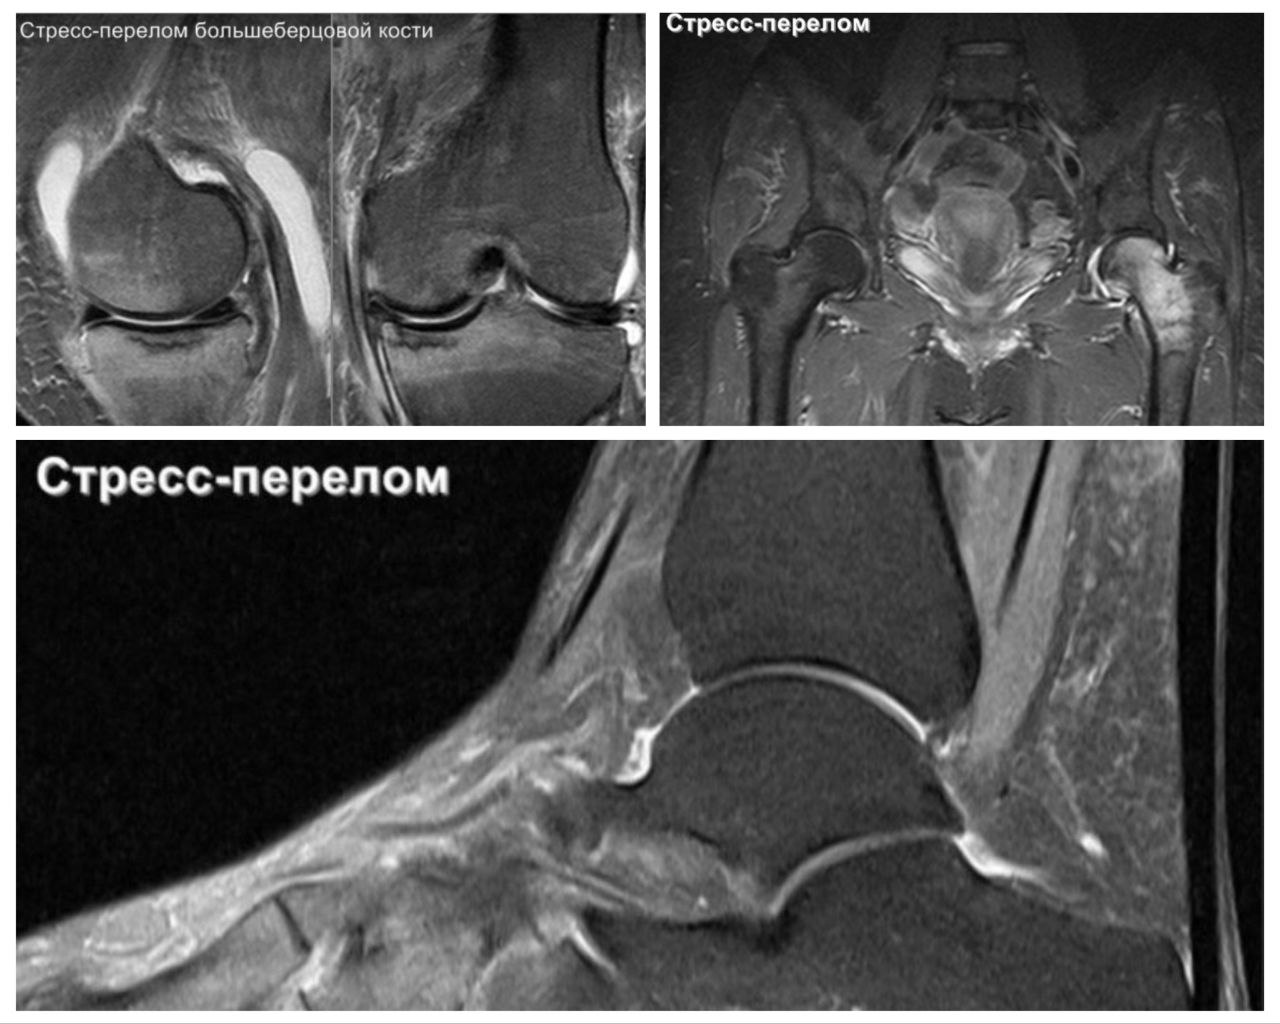

Например, когда организм сталкивается с новыми вирусами, то для синтеза новых клеток иммунной системы (которые рождаются в костном мозге – в костях), которые нужны для борьбы с вирусами и бактериями используются запасы веществ костной ткани и сам костный мозг, то происходит истощение костного мозга и костей, и кости слабеют и уже не могут переносить те же нагрузки как и раньше. Это истощение можно увидеть и на мрт, рентгенологи называют это жировая перестройка костного мозга, и иногда упоминают это в описании. Такая перестройка заканчивается переломом трабекул костной ткани, —  стресс-переломом с последующим отёком костного мозга и далее импрессионным переломом сустава.